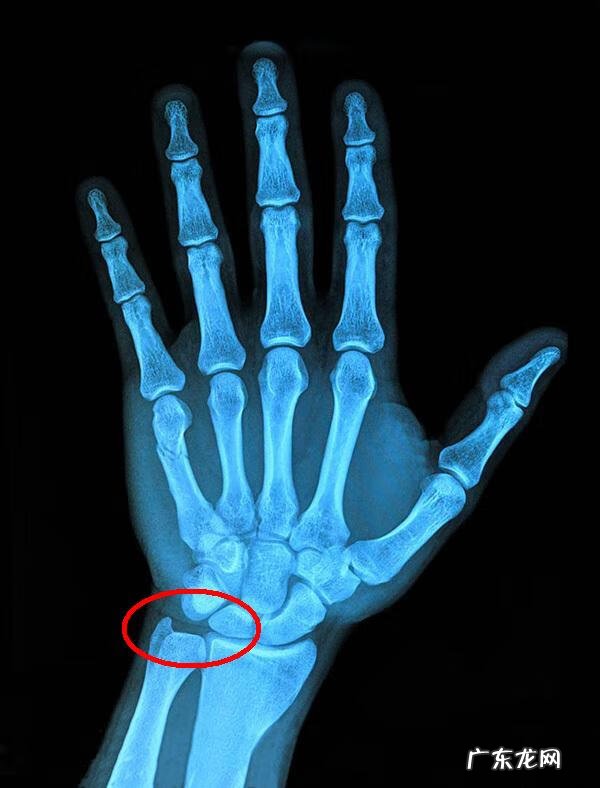

三角盘软骨位于腕关节小拇指一侧,主要起到稳定和缓冲的作用,类似半月板在膝关节中的作用,但比半月板结构复杂,是一个包括软骨、韧带、关节囊等在内的复合型组织 。三角软骨盘也是腕关节中最脆弱的环节,由于缺少血管的供氧和供血,在受伤后很难再生、痊愈 。

二、导致三角软骨盘损伤的各种原因中,慢性损伤较为常见,一般为压迫性损伤,一般是手背长期过度背伸,并承受较大压力导致的,比如做俯卧撑和卧推;腕部反复旋转时承受较大压力,也较容易导致三角盘软骨损伤;运动时热身不足,腕关节活动度不足、小臂肌肉僵硬,也容易导致三角盘软骨损伤 。急性损伤主要发生在跌倒手掌撑地时手背过度背伸,软骨盘的附着处组织撕断或分离,甚至使软骨盘本身撕裂 。

三角盘软骨损伤的症状表现为手腕旋转时疼痛,甚至不能旋转,手掌上下摆动时感觉疼痛,腕关节活动度受限 。在健身过程中主要表现在使用器械做推类动作时三角盘软骨处感觉疼痛 。